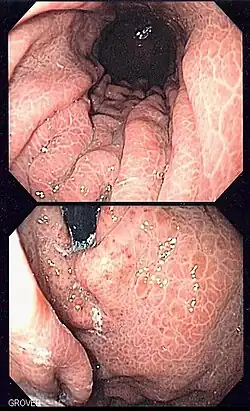

Gastropatia wrotna

Gastropatia wrotna, dawniej: gastropatia zastoinowa – schorzenie często pojawiające się w przebiegu nadciśnienia wrotnego. Powstanie krążenia obocznego powoduje zastój krwi w śluzówce żołądka, prowadzący do jej uszkodzenia. W efekcie dochodzi do przewlekłych krwawień, a często do zagrażających życiu krwotoków. Podobnym stanem, również związanym z nadciśnieniem wrotnym, są antralne poszerzenia naczyniowe.